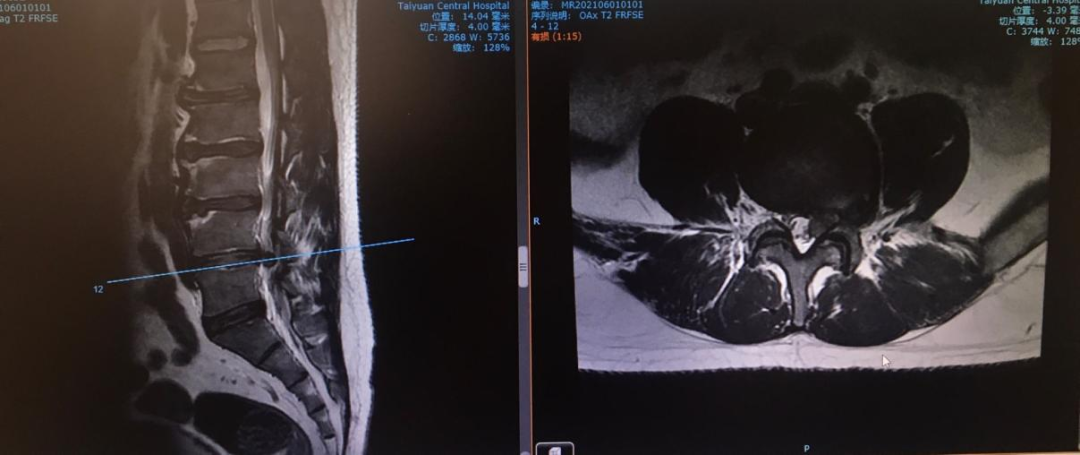

為了進一步搞清楚是什么原因,小梁慕名來到太原市中心醫院骨科汾東三病區就診。科主任林樹忠經過查體及仔細閱讀患者所帶影像學資料,診斷為腰椎間盤突出癥,完善腰椎MRI后進一步支持了當前診斷。

經科室專家團隊研究,結合患者31歲的年齡,最終為患者確定了“椎間孔鏡下腰椎髓核摘除術”的治療方案,此項手術具有創傷小,術后恢復快的優勢。

在積極完善術前準備后,主治醫生為患者在局麻下行椎間孔鏡手術治療。術中取出髓核,術后患者下肢疼痛癥狀完全緩解,感覺左腿較術前輕快許多。